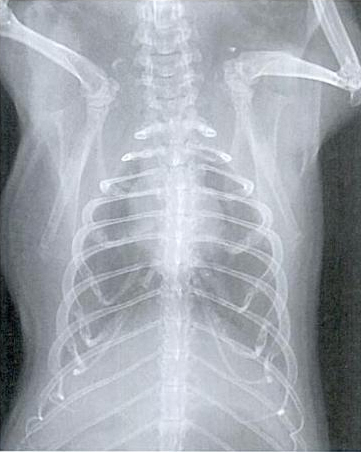

Slike dišnih puteva bez oboljenja:

Dijagnoza

Nedostatak tipičnih simptoma često otežava ranu dijagnozu. U slučaju bolesti se provode kliničke pretrage kao slušanje, mjerenje temperature, pulsa i promatranje frekvencije disanja. RTG pregled je koristan u slučaju dileme. Može pokazati da li i u kojem obimu postoje sjene u predjelu pluća. Kako se uzročnik ne može razlikovati, trebalo bi dati sekret iz nosa ili očiju, ili bris grla tj. nosa na pretrage kako bi se ustanovila kultura uzročnika i napravi antibiogram. U slučaju smrti, naročito ako je više životinja zaraženo, obdukcija bi imala smisla.